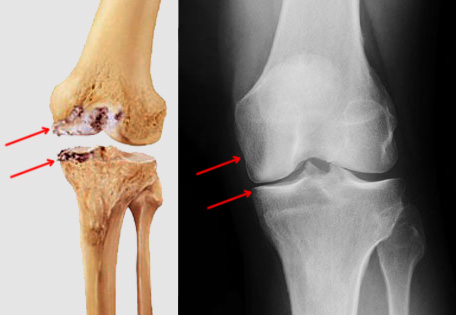

What is partial knee replacement surgery? Partial knee replacement is where the bone surfaces of only one compartment of the knee joint are removed and replaced with implants, as compared to that of multiple compartments in the case of a total knee replacement. It is a common treatment for unicompartmental arthritis. What happens during partial knee replacement? During partial knee replacement, the orthopedic surgeon makes a small incision to gain access to the affected compartment of the knee. He or she gently moves supporting structures of the knee out of the way and removes damaged cartilage and bone tissue from the surfaces of the tibia and the femur in the arthritic area. The surgeon then prepares these surfaces for the insertion of the prosthesis components, which are specifically sized for each individual patient’s joint. To Know more about partial knee replacement, book a consultation on 9111550303. Knee pain specialist in Andheri | Orthopedic doctor in Andheri | Ortho surgeon in Andheri | Best Orthopedic doctor in Andheri | partial knee replacement surgeon in Andheri